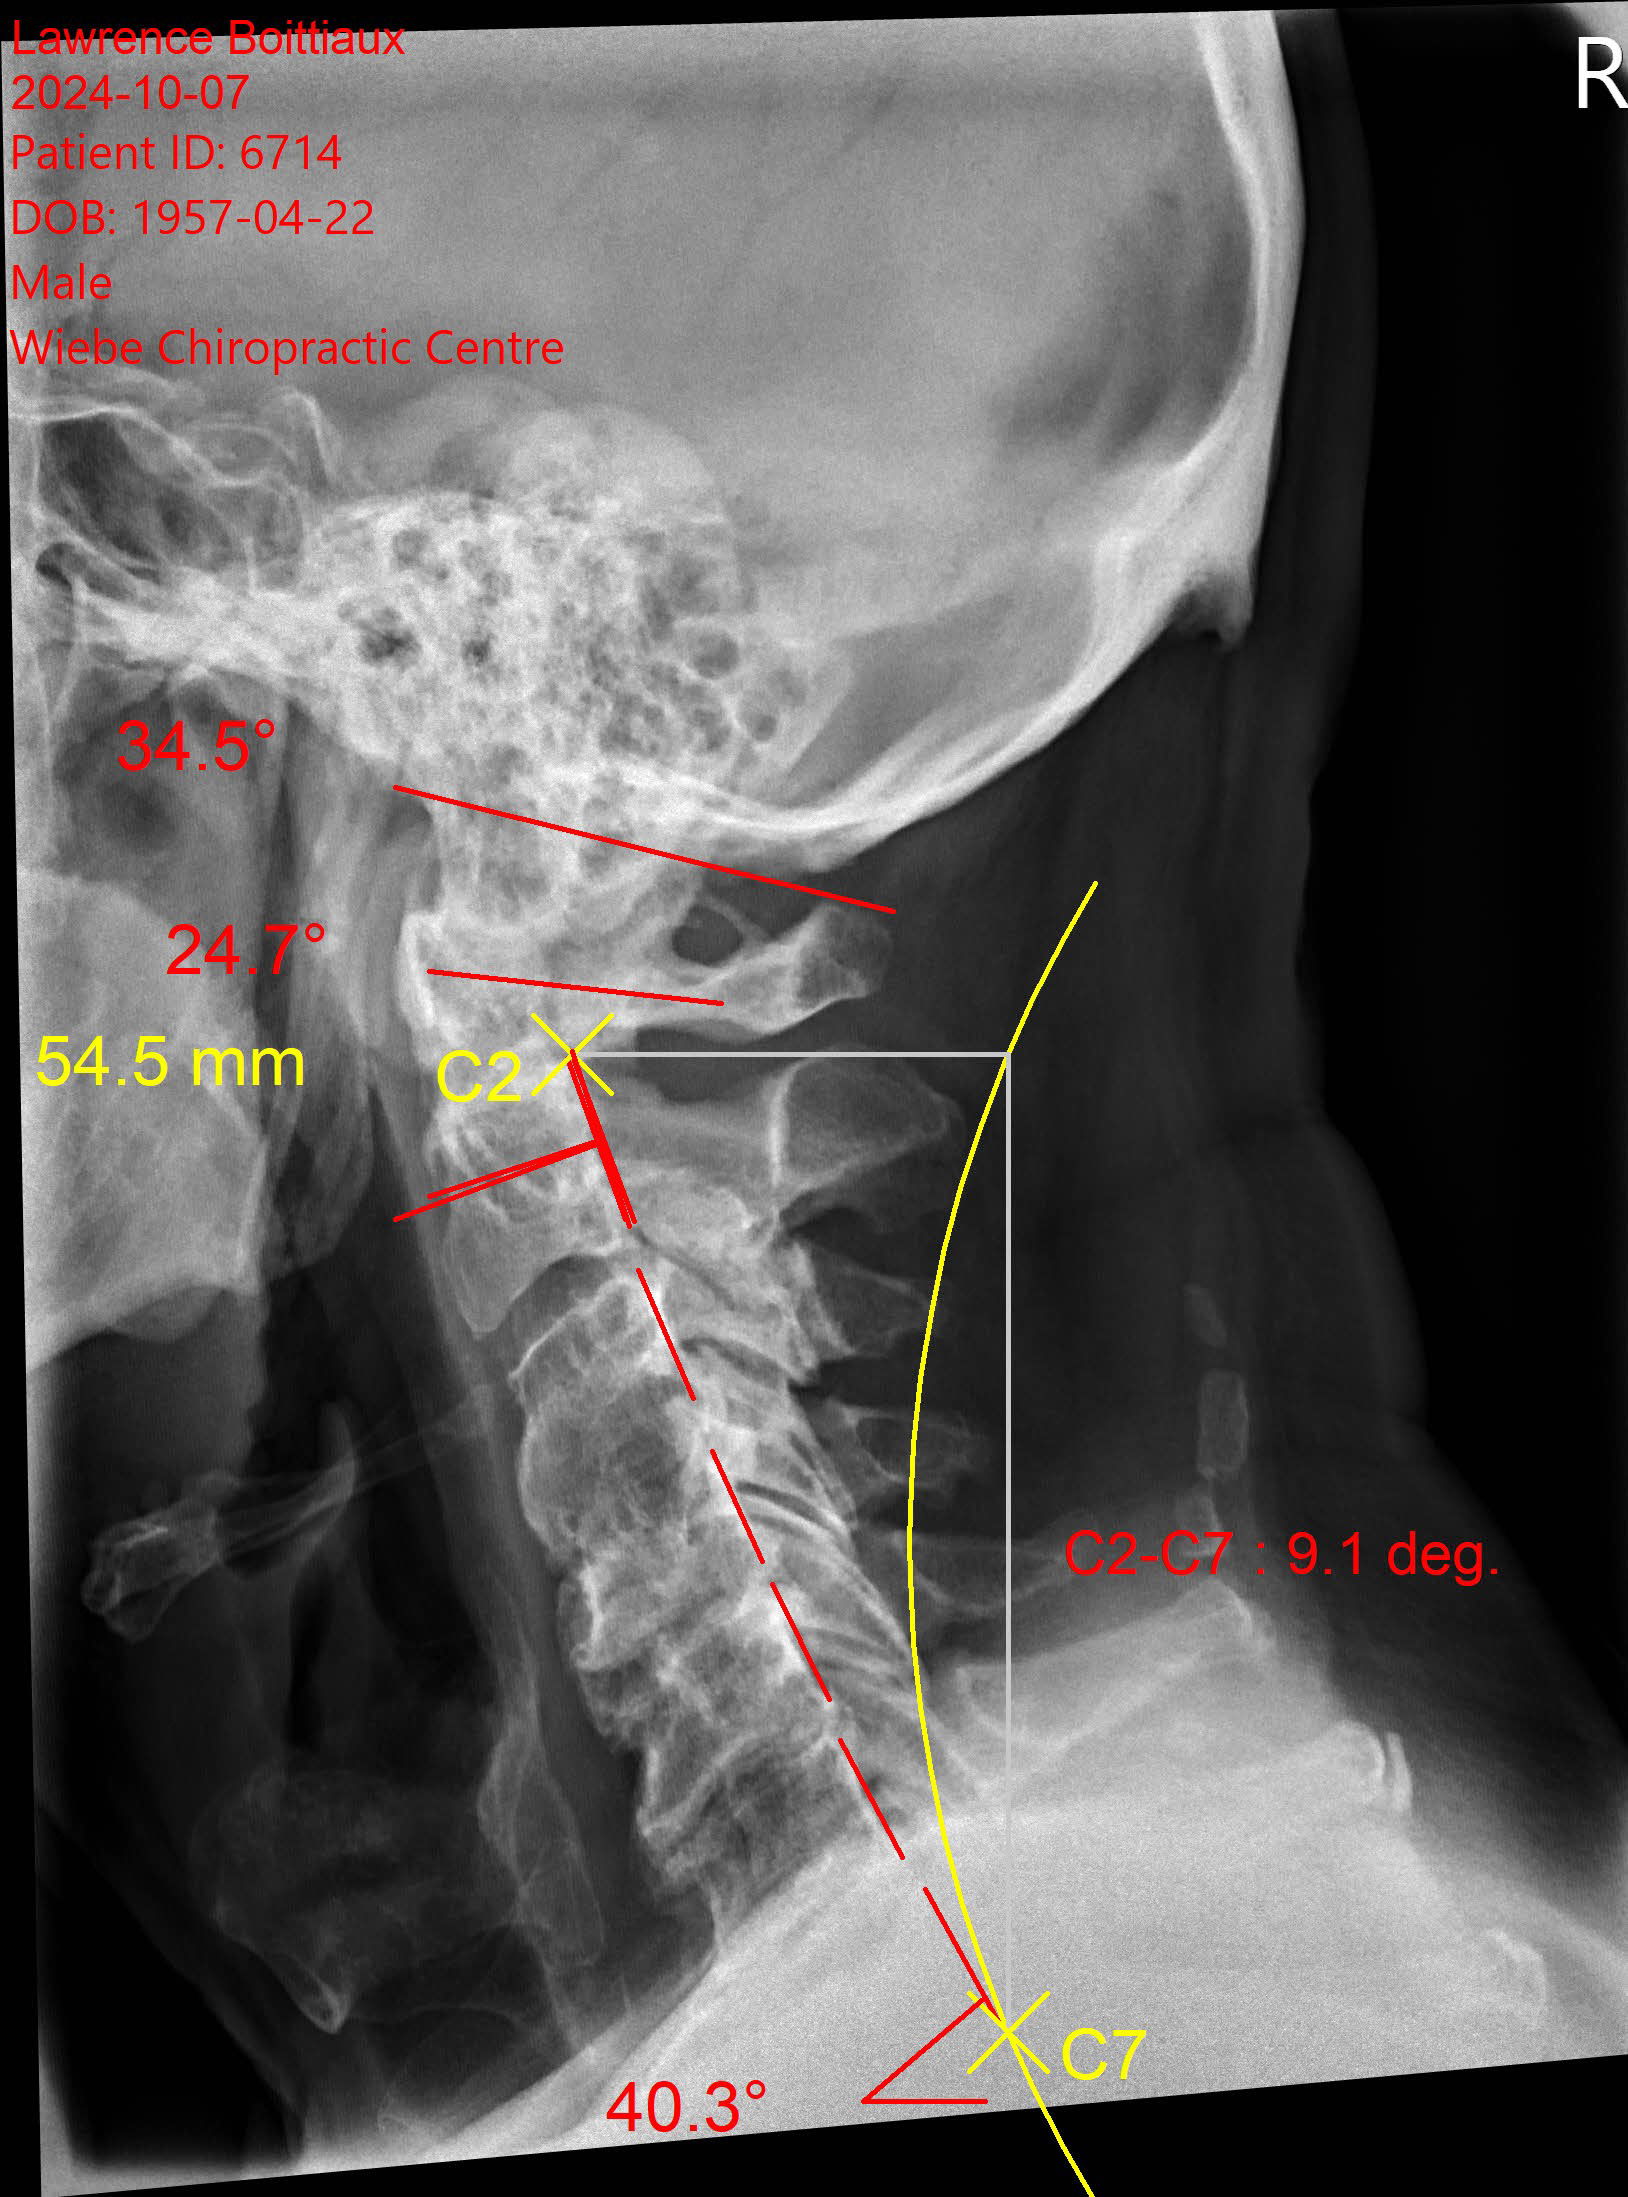

Analizar tu columna es muy importante para identificar la causa de tu dolor y prevenir cambios degenerativos o estructurales que puedan afectar tu calidad de vida y adecuado funcionamiento de tu cuerpo.

utilizamos los estudios competentes para brindar un diagnóstico preciso sobre las condiciones de tu columna.